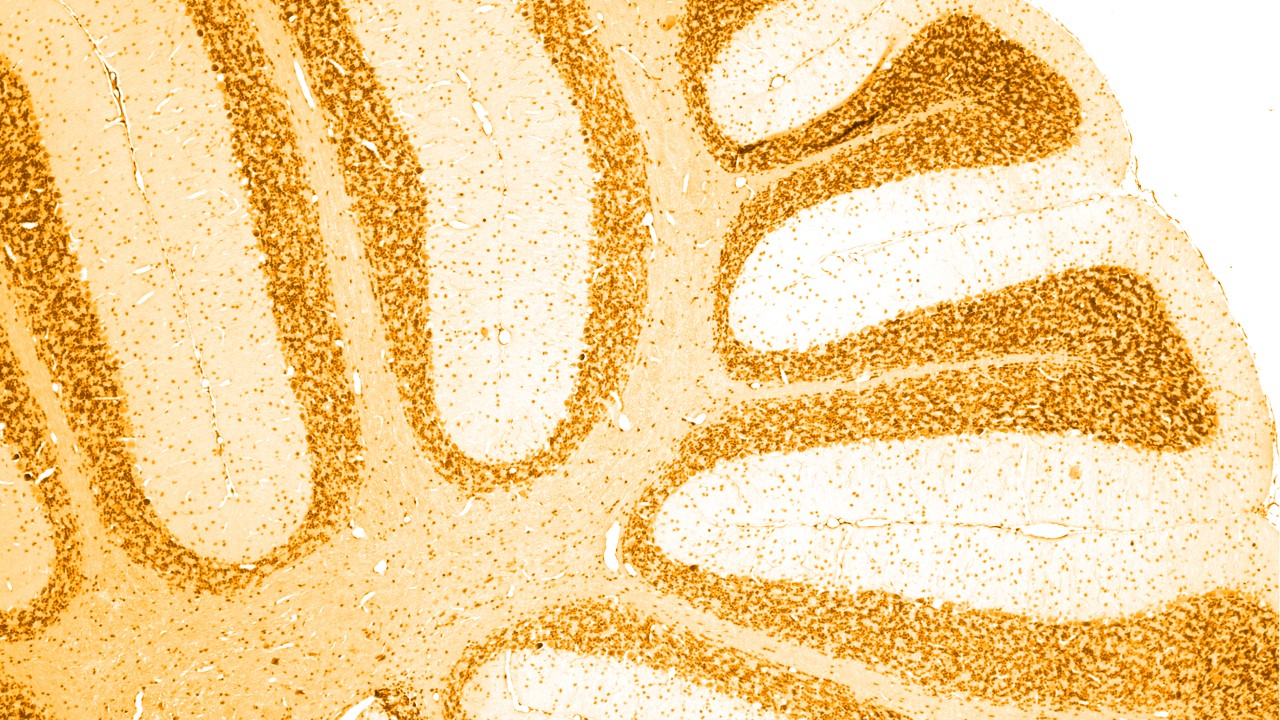

Neurologiset häiriöt ovat keskus- ja ääreishermoston sairauksia. Toisin sanoen aivot, selkäydin, hermot ja lihakset säätelevät ja koordinoivat kehon toimintoja.